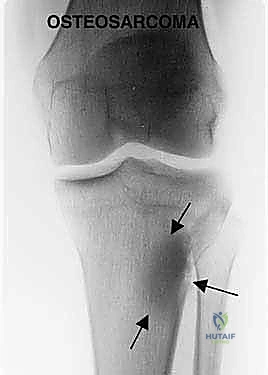

* الساركوما العظمية (Osteosarcoma): وهو النوع الأكثر شيوعاً، ينشأ في الخلايا المكونة للعظم، ويتميز بنموه السريع والعدواني وتدميره للعظم المحيط.